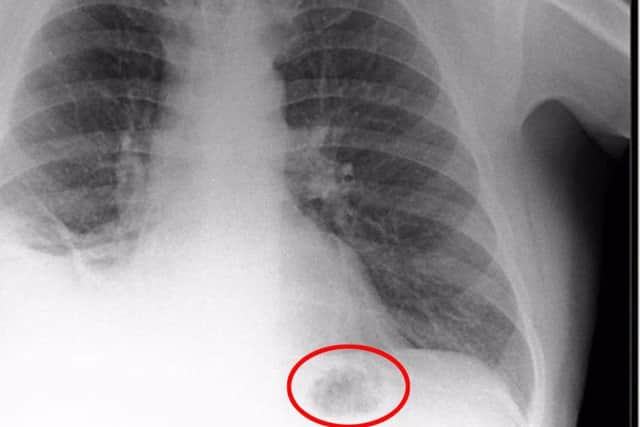

في اليمين اليسار رئة بول قبل التشافي وفي اليمن نلاحط اختفاء الظل الغريب